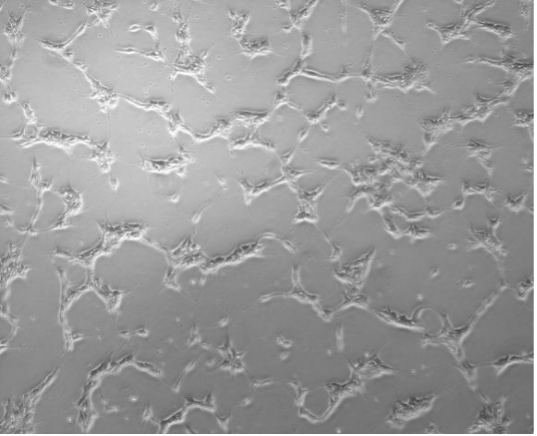

| 科研级 iPSC 细胞株-男性 | JY01-012-1 | 29岁,男性 | 1×10^6/支 | GEMi001-A |

| JY01-014-1 | 28岁,男性 | 1×10^6/支 | GEMi002-A | |

| JY01-160-1 | 25岁,男性 | 1×10^6/支 | GEMi005-A | |

| JY01-211-2 | 25岁,男性 | 1×10^6/支 | GEMi016-A | |

| JY01-212-1 | 26岁,男性 | 1×10^6/支 | GEMi017-A | |

| JY01-213-1 | 42岁,男性 | 1×10^6/支 | GEMi018-A | |

| JY01-215-1 | 32岁,男性 | 1×10^6/支 | GEMi020-A | |

| JY01-216-1 | 35岁,男性 | 1×10^6/支 | GEMi021-A | |

| JY01-217-1 | 34岁,男性 | 1×10^6/支 | GEMi022-A | |

| JY01-218-1 | 23岁,男性 | 1×10^6/支 | GEMi023-A | |

| 科研级 iPSC 细胞株-女性 | JY01-135-1 | 24岁,女性 | 1×10^6/支 | GEMi004-A |

| JY01-201-1 | 27岁,女性 | 1×10^6/支 | GEMi006-A | |

| JY01-202-1 | 25岁,女性 | 1×10^6/支 | GEMi007-A | |

| JY01-203-1 | 30岁,女性 | 1×10^6/支 | GEMi008-A | |

| JY01-206-1 | 25岁,女性 | 1×10^6/支 | GEMi011-A | |

| JY01-208-1 | 40岁,女性 | 1×10^6/支 | GEMi013-A | |

| JY01-209-1 | 50岁,女性 | 1×10^6/支 | GEMi014-A | |

| JY01-210-1 | 23岁,女性 | 1×10^6/支 | GEMi015-A | |

| JY01-046-3 | 28岁,女性 | 1×10^6/支 | GEMi026-A |